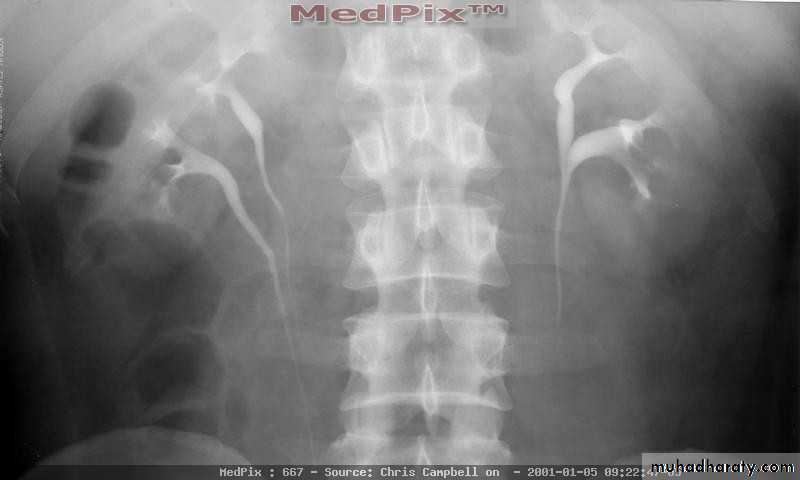

Cystic disease of the kidneys

Polycystic kidney disease :

The kidney is one of the most common sites in the body for cysts

Congenital cystic kidney (polycystic kidney) (Adult cystic renal disease)

Autosomal dominant, transmitted by either parents, 50% of offspring affected.

Both kidneys replaced by large no. of cysts of variable size which make the kidney of large size.

The cysts contain clear fluid but sometimes blood.

The cysts progressively increase in size causing pressure atrophy of the renal parenchyma and pressing the ureter.

15% associated with cystic disease of liver, lung, pancreas or spleen.

Clinical pictures:

Rarely gives clinical manifestation before 4o years

Asymptomatic: diagnosed accidentally.

Pain: due to pedicle stretching, stone, ureteric obstruction, bleeding inside cyst or infection.

Hematuria: cyst distention and rupture to the collecting system.

Infection: renal or cyst infection causes fever, rigor and loin pain.

Hypertension: in 70%, Unknown cause.

Renal impairment: anorexia, headache, nausea, vomiting, drowsiness and coma.

Renal enlargement: large knobby palpable kidney

Diagnosis: Family history of polycystic disease.

U/S, IVU, CT scan, MRI